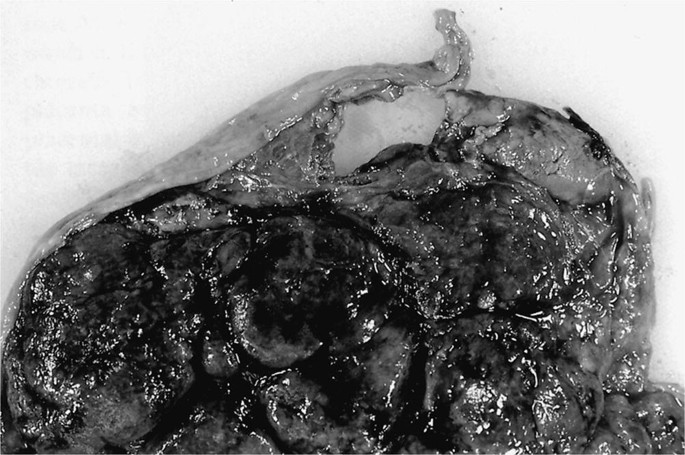

3. Placenta fenestrata. The central area of the placenta has a distinct... | Download Scientific Diagram